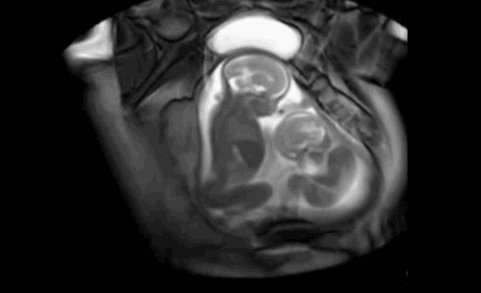

随着医学技术的进步,现在通过仪器就可以看到宝宝在准妈妈肚子里的状态,但你绝对想不到下面这些令人难以置信的照片竟展示了一对双胞胎在子宫内打闹和交谈。简直惊呆了!

请看下面的动图,真是太萌了

一开始小baby连续出招

大baby不为所动

接着小baby加猛攻势

大baby开始有所回应

小baby不依不饶,继续战斗

大baby好像开始说话了

猜猜他在说什么呢

把这个动图看了一遍又一遍

来自弟弟那小小的一脚

可能是他们之间某种独特的交流方式

是在进行拳击比赛

或是争抢狭小的空间

无论哪种方式

这都是生命的奇迹啊